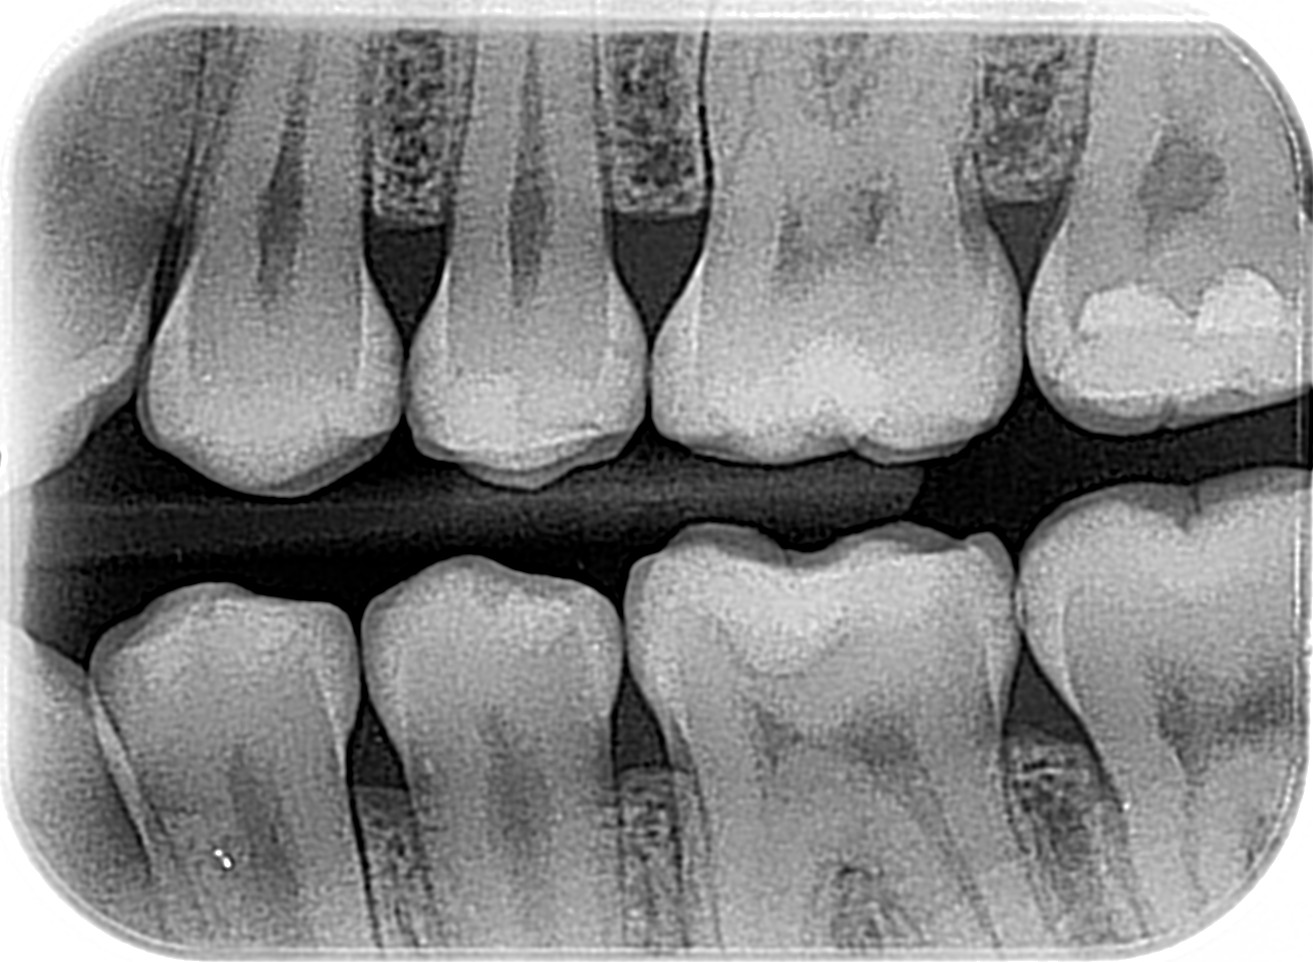

Radiografía Bitewing

Bitewing Bilateral

Propósito principal detección de caries: Es la herramienta "Gold standard" para encontrar caries que no son visibles a simple vista, especialmente en áreas de contacto (premolares y molares) y visualizar desajustes cervicales.